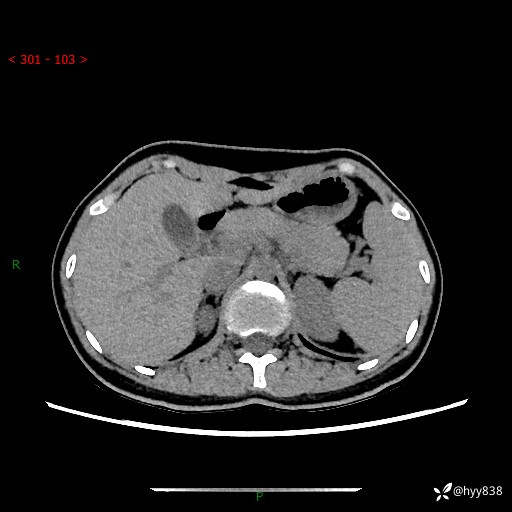

性别:女

年龄:23岁

简要病史:外院发现肝结节,来我院进一步增强确诊

上腹部CT平扫+增强

肝囊肿 (68)